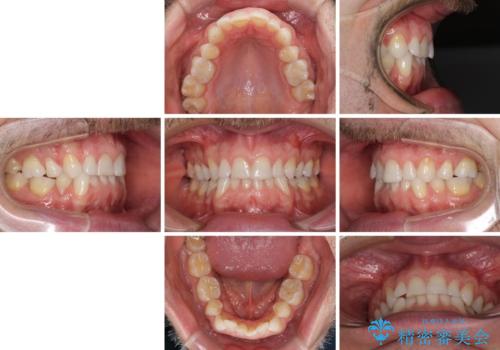

- 上下前歯の叢生を気にして来院された患者様です。

抜歯矯正をした後戻りということで、歯列不正はそれほど大きくなかったため、インビザライン・ライトを用いて矯正治療を行うこととしました。

前歯のデコボコが残っており、シミュレーション通りに動いていない部分がありましたが、再矯正であることやご本人の満足いくところまでデコボコが改善されたとのことで、治療を終了することとしました。